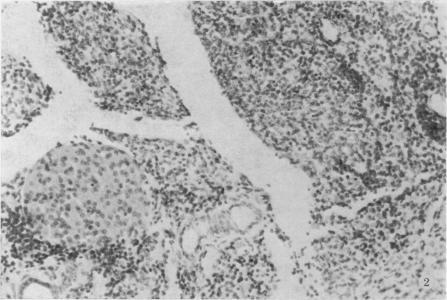

Coxsackievirus B3 causes foetal wastage and growth retardation in mice which may be attributed to the action of the virus in destroying the maternal exocrine pancreas. Injection of virus on Day 4 or 8 of gestation caused greater foetal wastage than injection at 12 days. Foetal and placental weights in infected animals were less than in the controls but did not vary according to the time of infection. Little support is offered for the view that the mouse foetus differs in its susceptibility to Coxsackievirus B3 according to the stage in gestation of infection.

柯萨奇病毒B3可导致小鼠出现胚胎死亡和生长发育迟缓,这可能归因于该病毒破坏母体胰腺外分泌部的作用。在妊娠第4天或第8天注射病毒比在第12天注射导致更多的胚胎死亡。感染动物的胎儿和胎盘重量低于对照组,但并不随感染时间而变化。关于小鼠胎儿对柯萨奇病毒B3的易感性因感染时的妊娠阶段而异这一观点,几乎没有证据支持。